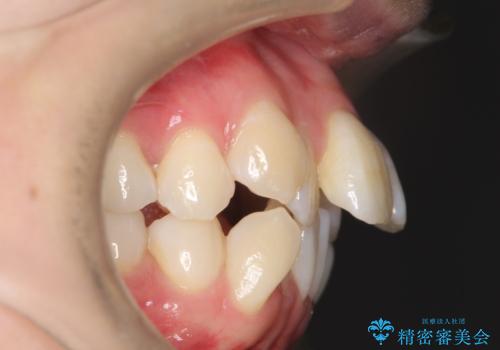

- 出っぱによる口元の閉じにくさを主訴に来院されました。上顎の出っ歯と上下顎叢生も認められたため、上下顎両側4番抜歯を行い、ワイヤー矯正で治療する治療計画を立てました。

上顎にはMI(マイクロインプラント)を埋入して固定源とすることで出っ歯の改善を図りました。

少しスペースクローズに時間がかかりましたが、MIを用いたワイヤー矯正で

主訴である出っ歯と叢生が改善されました。口も閉じやすくなり、スッキリとした口元になりました。